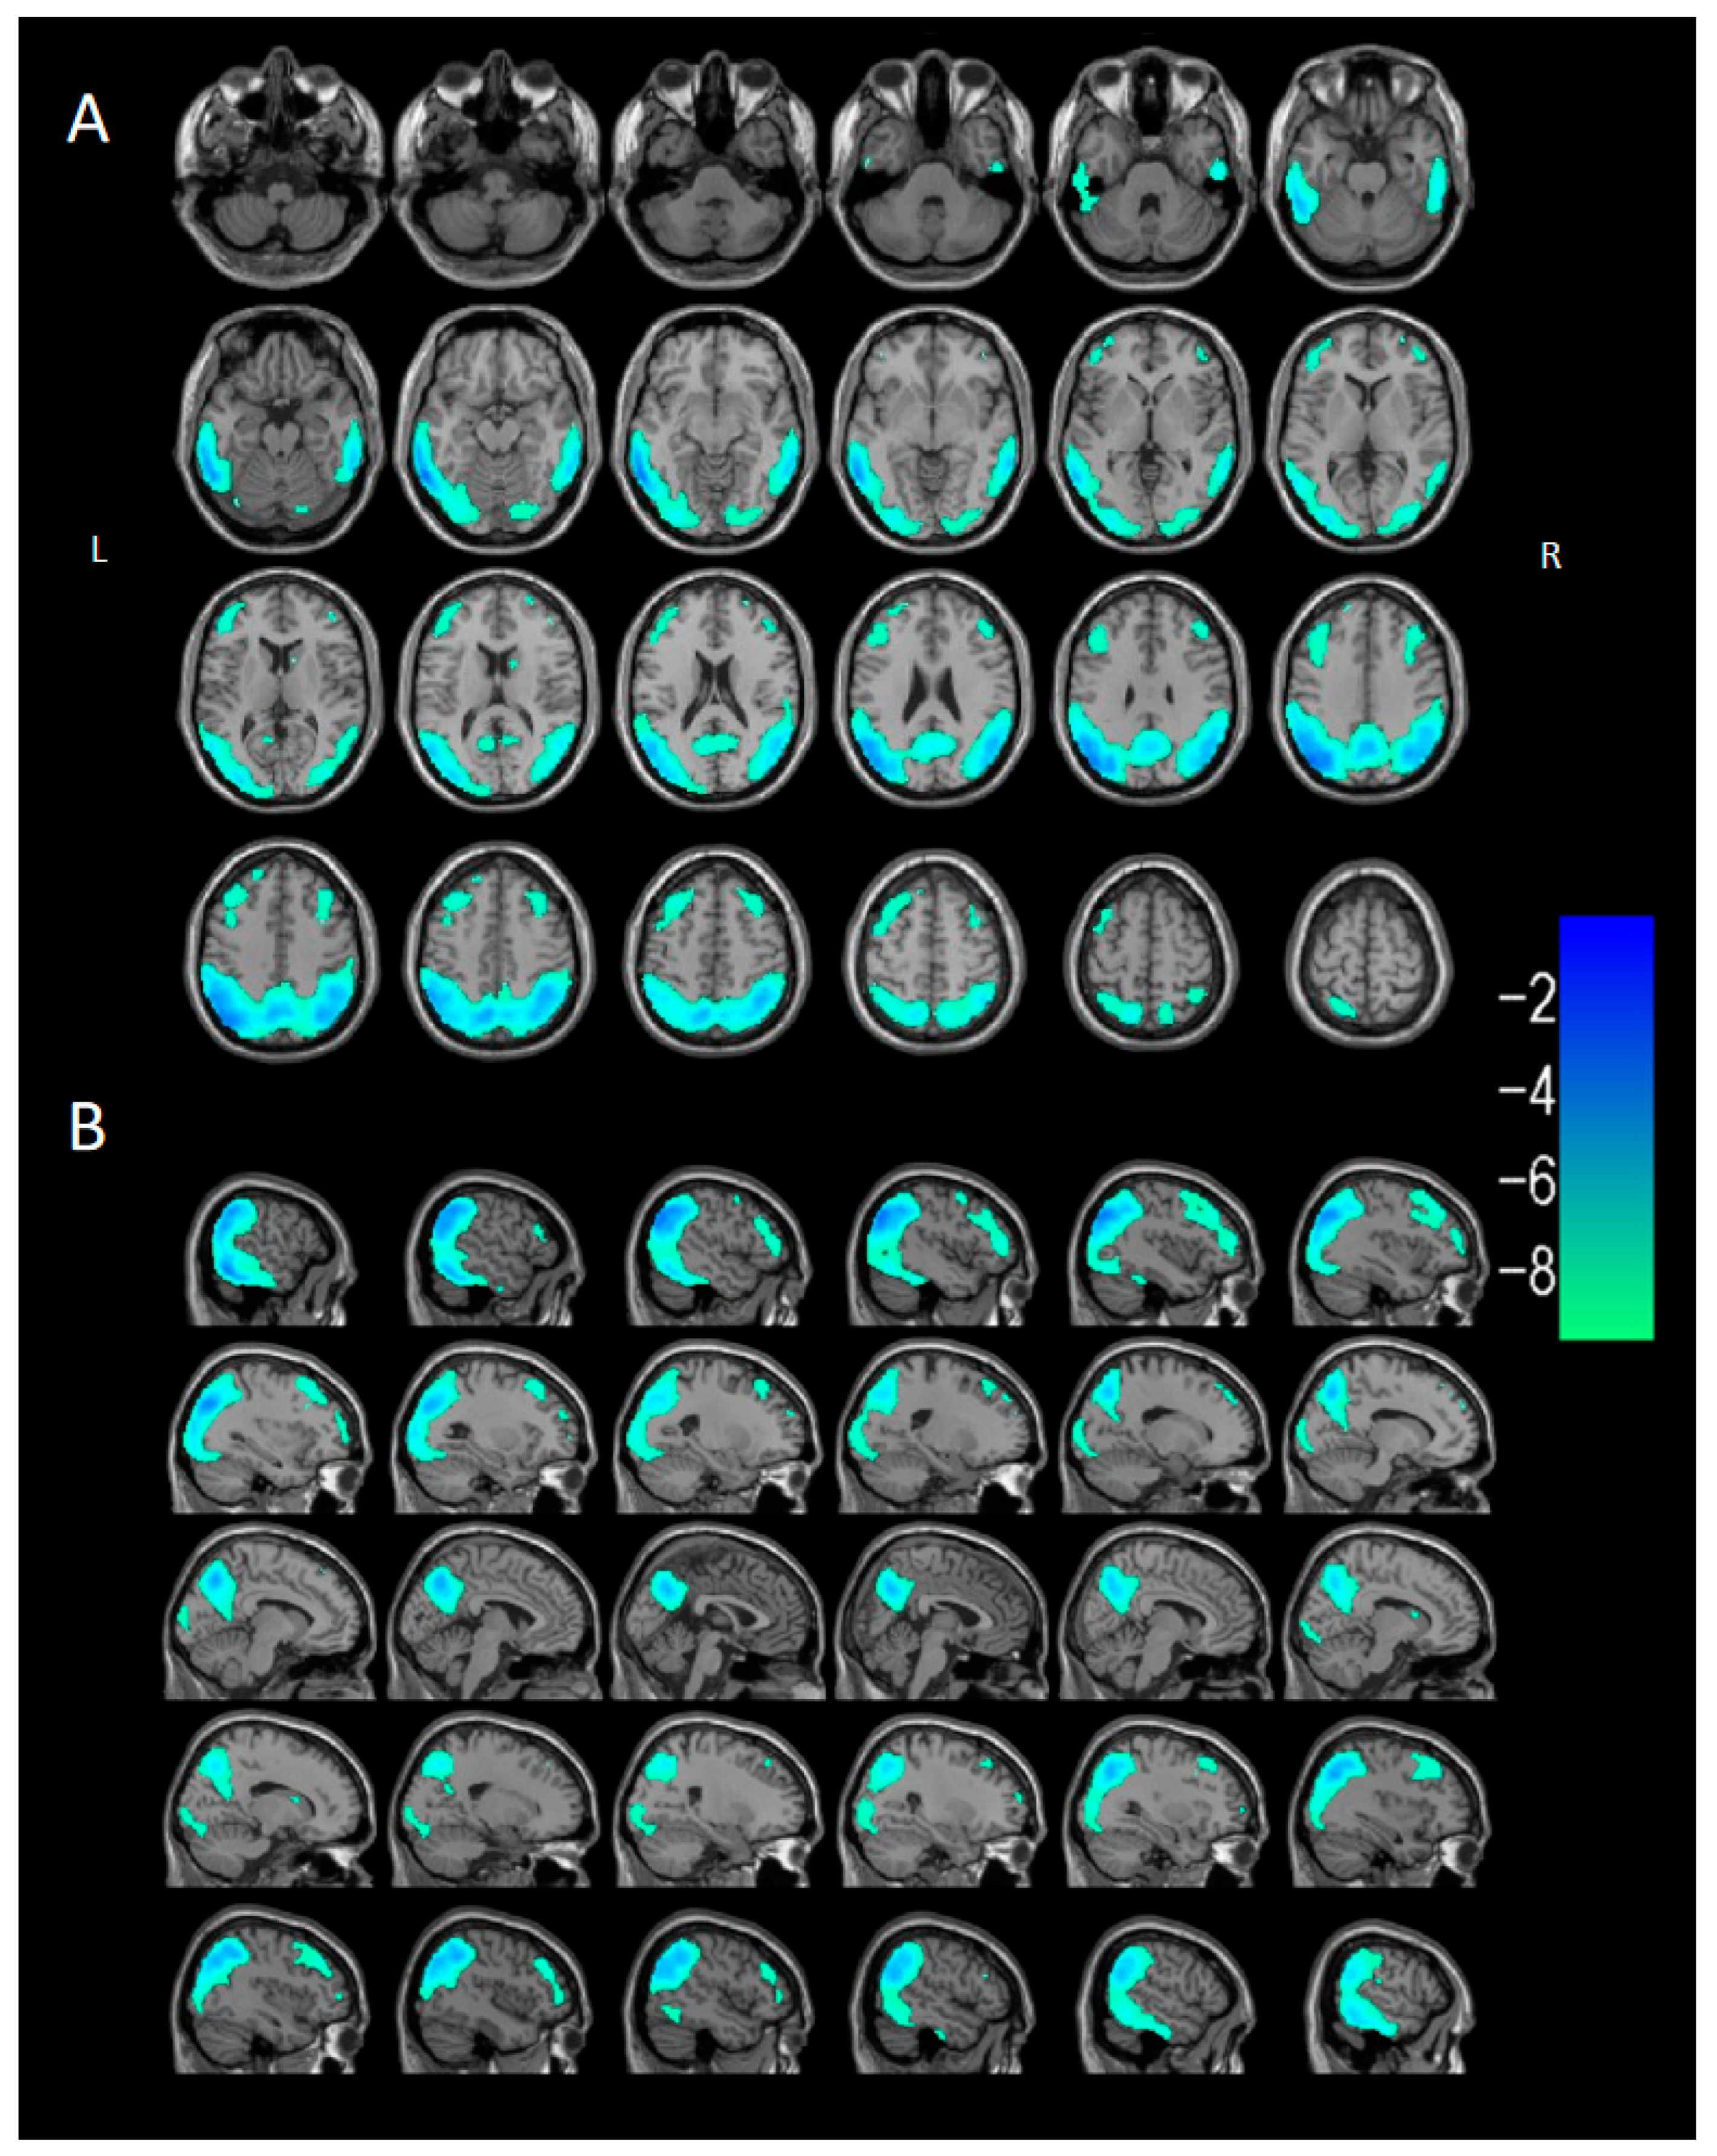

3.2.3. Voxel-Based Semi-Quantitative Analysis